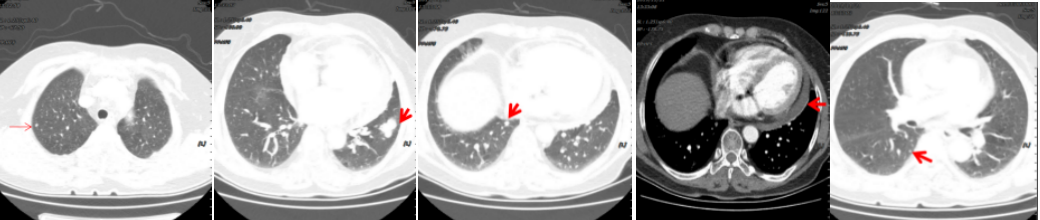

病例简介 该病例是一个肺腺癌(cT4N0M1a)IVa期患者,合并有高血压、冠心病、糖尿病。一线治疗前基因检测结果提示EGFR 19del(+)。一线治疗(埃克替尼片125mg tid)疗效评估为PR、PFS 22个月。一线治疗前基因检测结果提示EGFR 19Del(+)、T790M(+)。后入组D0316(贝福替尼)在EGFR阳性局部晚期或转移性非小细胞肺癌的II期临床试验(IBIO-102项目)。治疗先后由D0316 75mg qd更改方案为D0316 100mg qd,疗效评估为PR,、PFS>32月。至今患者仍持续用药随访中。 Part 1 基本信息 患者:女性;74岁。 主述:反复咳嗽3年,加重伴呼吸费力4月,于2018-1-17就诊。 既往史: 高血压病史10年,服用络活喜、厄贝沙坦氢氯噻嗪、美托洛尔控制血压;冠心病,冠脉支架置入术后4年;糖尿病史2年;否认其他病史。 Part 2 诊疗经过 治疗前辅助检查 2018-1-17查体:血压129/85mmHg;无明显阳性体征。 实验室检查 2018-1-18:血CEA 9.9ng/ml、Cyfra21-1 4.3ng/ml;SCC、NSE、Pro-grp均正常;血常规(Hb 109g/l)、肝肾功能、crp正常。 影像学检查 2018-1-8胸部CT:两肺多发结节,考虑MT伴转移,对照2017-10-4片增大,冠脉钙化,左侧部分肋骨陈旧性骨折,胆囊结石; 2018-1-22腹部B超:脂肪肝倾向,胆囊结石,两肾囊肿,两侧肾上腺未见明显异常回声; 2018-1-21头颅MRI:平扫+增强未见明显异常; 2018-1-23骨ECT:全身骨显像未见明显转移征象。 治疗前病理诊断 肺腺癌(cT4N0M1a) IVa期; 2018-1-18肺穿刺及病理:CK7( ++++ );NapsinA( ++++ ) ;TIF-1(++++);EGFR 19Del(+) ;ALK(-) 。 治疗前临床诊断 肺腺癌(cT4N0M1a) IVa期;PS 1分;EGFR 19Del(+);冠心病、冠脉支架置入术后;高血压病;糖尿病。 一线治疗 治疗方案:2018-1-26开始,埃克替尼片125mg tid。 疗效评估(PR,PFS 22月 ) 埃克替尼治疗11.3个月,两肺结节减少、缩小,达到PR (2018-12-4);治疗22个月,左下肺结节增大、肺内新发小结节、新发心包积液,出现PD(2019-11-21)。 2018-1-18 治疗前基线 2018-12-4 埃克替尼 11.3月(PR) 2019-11-21 埃克替尼 22月(PD) 一线治疗后辅助检查 实验室检查 2019-11-29血CEA 8.4ng/ml ;Cyfra21-1 4.8ng/ml;SCC、NSE、Pro-grp均正常。 2019-12-13血生化肌酐84umol/l;肝功能正常;血常规正常。 影像学检查 2019-12-4头颅MRI平扫+增强:脑内少许腔梗灶; 2019-12-2骨ECT:全身骨显像未见明显转移征象; 2019-12-4腹部增强CT:胆囊结石,右肾上腺及胰腺钙化灶,两肾囊肿。 生理学检查 2019-12-13 ECG:窦性心律,T波改变; 2019-12-13心超:左室轻度增大,左室壁偏厚,左房轻度增大,轻度肺动脉高压伴轻度三尖瓣返流,心包积液,脏层心包增厚,左室舒张功能轻度减退。 一线治疗后病理诊断 2019-11-29分子病理(ARMS法):EGFR 19Del(+) ;T790M(+)。 临床诊断 肺腺癌(cT4N0M1a);IVa期;肺、心包转移;PS 1分;EGFR 19Del(+);T790M(+);冠心病;冠脉支架置入术后;高血压病;糖尿病;肾功能不全。 二线治疗 入组D0316(贝福替尼)在EGFR阳性局部晚期或转移性非小细胞肺癌的II期临床试验(IBIO-102项目)。 治疗方案 2019-12-19开始D0316 75mg qd,于2019-12-24至2020-1-15出现头痛、肩背痛1级AE,自行缓解; 2020-1-13开始D0316 100mg qd; 合并用药有针对糖尿病药物西格列汀片 50mg qd;针对高血压药物氨氯地平5mg qd、厄贝沙坦氢氯噻嗪片1片qd、美托洛尔缓释片47.5mg qd;针对冠心病药物西洛他唑 50mg bid;针对睡眠障碍药物氯硝西泮片1mg qn、艾司酉酞普兰片10mg qd、喹硫平片50mg qd。 安全性评估 疗效评估(PR, PFS>32月 ) D0316 治疗6周就达到PR,患者左下肺靶病灶缩小,两肺小结节稳定、部分缩小(2020-1-28);治疗30周仍为PR,且心包积液减少(2020-7-13);治疗30.5月仍为PR,右下叶背段胸膜下结节缓慢进展(2022-6-30)。 2019-11-21 D0316 治疗前基线 2020-1-28 D0316 治疗6周(PR) 2020-7-13 D0316 治疗30周(PR) 2022-6-30 D0316 治疗30.5月(PR) 2022-6-30腹部增强CT:胆囊结石,右肾上腺及胰腺钙化灶,两肾囊肿。 目前D0316(贝福替尼) 100mg qd 治疗中, PS 1分。